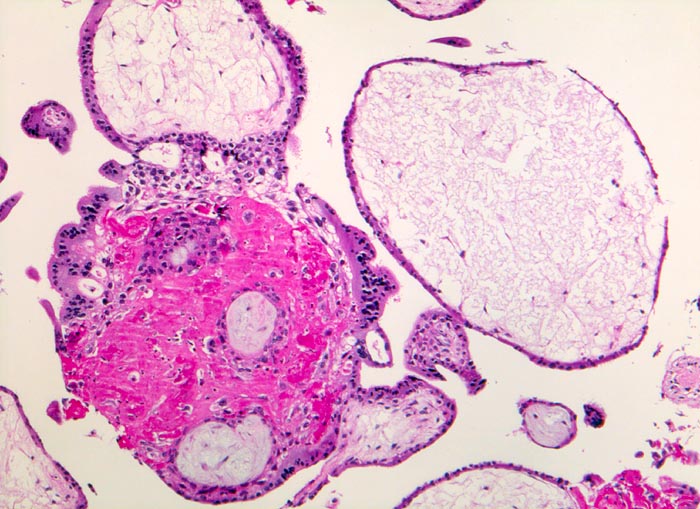

Chromosomenaberrationen verursachen nicht nur beim Feten, sondern auch an der Chorionzotte morphologisch fassbare Entwicklungsstörungen: mangelnde Verzweigungen, wandernde Trophoblastzellen im Stroma, mangelhafte Vaskularisation, hydropische Alteration des Stromas und herdförmige Atrophie oder auch Hyperplasie des Trophoblasten sind typische Befunde bei einer Chromosomenaberration. Aborte mit Triploidie zeigen in der grossen Mehrzahl das Bild einer Partialmole. Eine Tetraploidie kann das Bild einer Windmole (=Windei), einer Embryonalmole oder seltener einer Partialmole verursachen. Autosomale Trisomien können ebenfalls als Windmole oder als Embryonalmole imponieren. In nur etwa 25% aller Spontanaborte sind bei der pathomorphologischen Untersuchung ein Embryo, Embryofragmente oder ein Nabelschnuranteil nachweisbar. Die morphologische Untersuchung des Abortmaterials stellt eine wichtige Ergänzung zu den klinischen Befunden dar.

• Vergrösserte Plazentarzotten mit hydropischem Zottenstroma.

• Vereinzelt Zytotrophoblasteinschlüsse im Stroma.

• Vorwiegend einschichtiges Zytotrophoblastepithel ohne Atypien und mehrkerniger Synzytiotrophoblast. Physiologische polare Trophoblastproliferate.

• Kein Embryo.